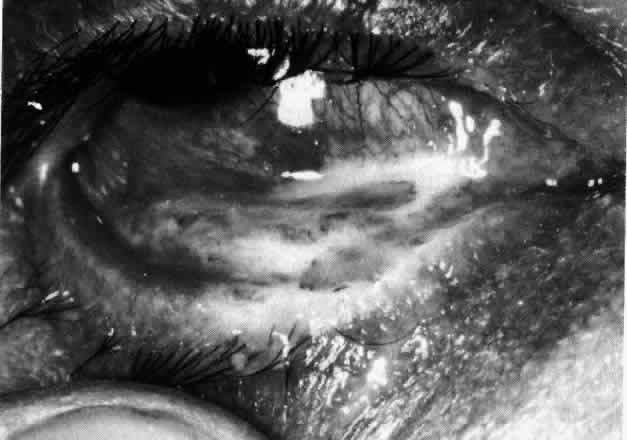

Necrotizing Anterior ScleritisdWithout Adjacent Inflammationd(Scleromalacia Perforans)

Necrotizing anterior scleritis without adjacent inflammation appears to be a well-defined condition with little relation in clinical features to necrotizing scleral disease, even though the pathology is similar and the final result is the same. Scleromalacia perforans is characterized by the almost total lack of any symptoms. It occurs almost exclusively in patients with long-standing polyarticular rheumatoid arthritis, the majority of whom are female (Figs. 49 and 50; Color Plate 1E).

Fig. 49. A white necrotic plaque developing in an area of sclera with practically no surrounding inflammation in a 60-year-old woman who had had Crohn's disease for 17 years.

Fig. 50. Scleromalacia perforans after treatment. The very thin sclera is covered by conjunctiva only and a few remaining large blood vessels. (Courtesy of Mr. HE Hobbs)

The anterior sclera loses its covering of episclera and develops an area of yellow-white necrotic slough over many months; this eventually separates or is absorbed, leaving the underlying choroid covered by either conjunctiva or nothing at all. As with necrotizing disease, the choroid does not bulge into this ectatic area; but unlike necrotizing disease, spontaneous healing of even small perforations is very limited once the necrotic tissue has been removed (see Fig. 50).

Fluorescein angiography is not helpful, except to indicate areas of vascular closure in an otherwise extremely thin, atrophic episcleral tissue.4 The formation of a sequestrum appears to be caused by arteriolar closure as opposed to the venular disease seen in the other forms of necrotizing scleritis.